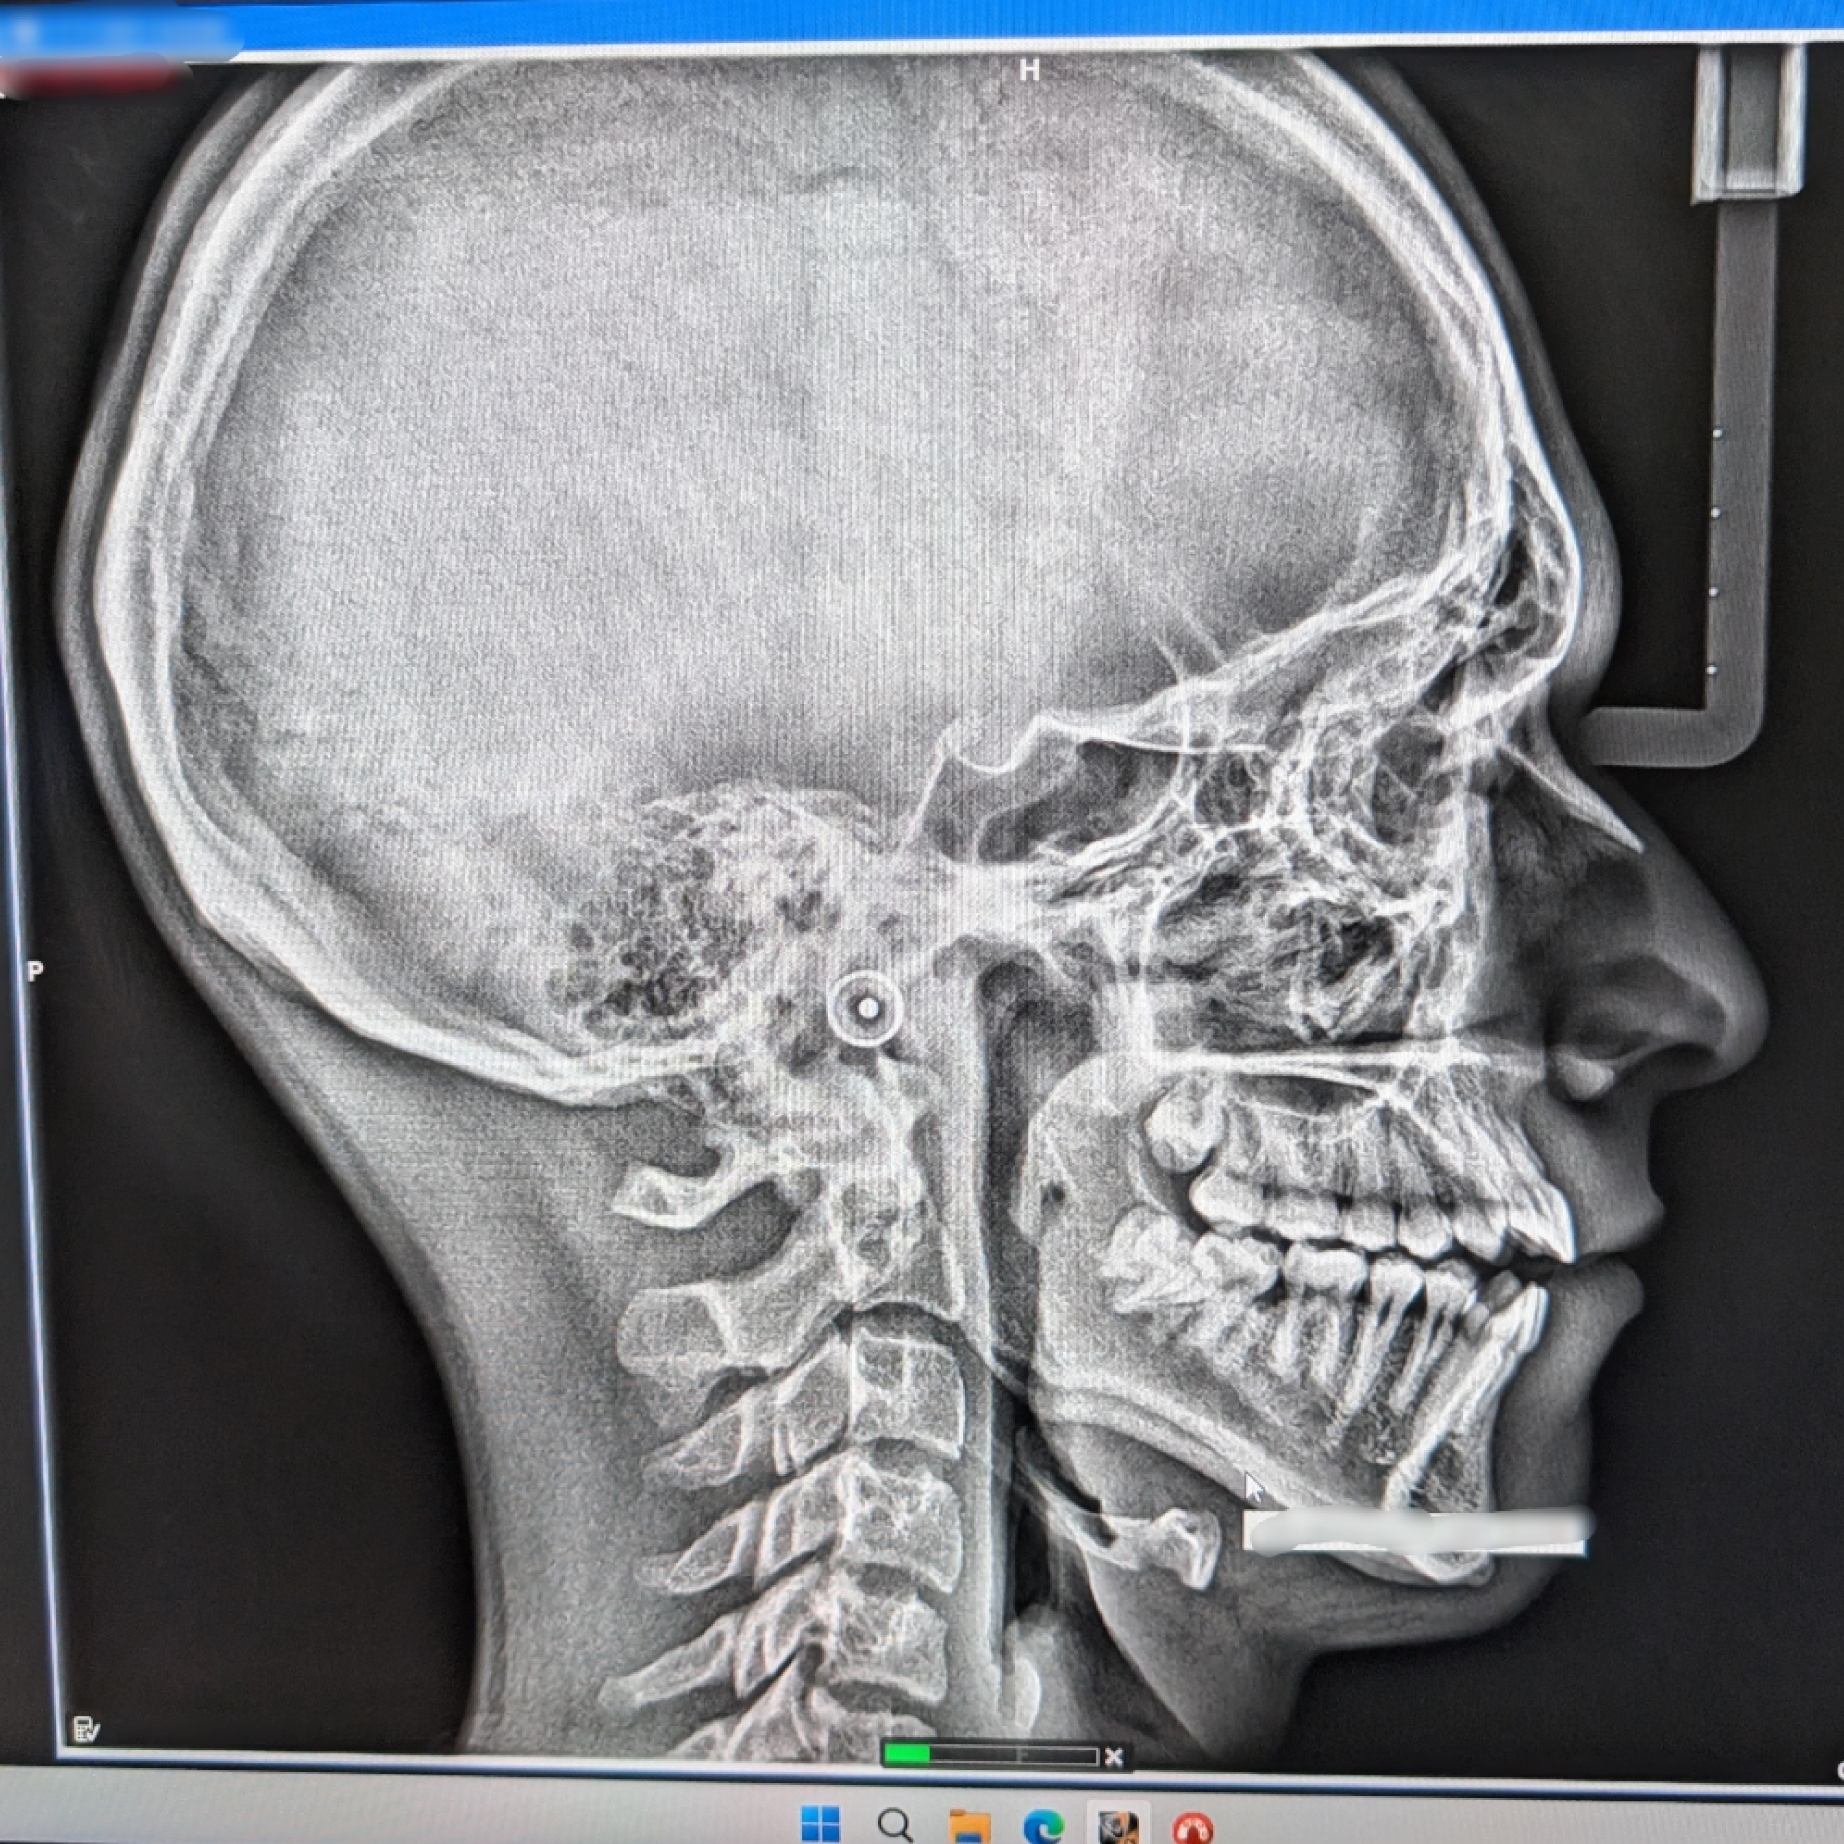

Orthodontist told me Invisalign might not fix my teeth (SIDE X-RAY)

I'm 17, 180 and LTN. Had crooked teeth since probably 12 y. o. (Horrible open bite + crowding). Finally managed to get an appointment at a place where they do Invisalign, got a front and side x-ray, and the orthodontist redirected me to a different place cause he told me he is afraid he is not competent enough for this 😭 Asked him about MSE , and he told me I could have it (narrow smile and poor maxilla projection 💀) but it would cause crossbite cause my upper arch would be wider than lower